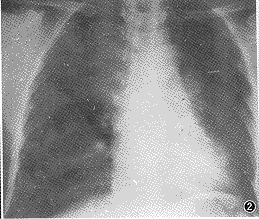

3、X线检查X线特点为均匀致密阴影,占据一侧胸部、一叶或肺段。阴影无结构,肺纹理消失及肺叶体积缩小。一侧或大片肺不张时可见肋间变窄、胸腔缩小。阴影位置随各肺叶肺不张的部位而异。下叶肺不张在正面胸片中成三角形阴影,位于脊柱与膈肌之间,在侧片中则靠近后胸壁。若系上叶肺不张,则正面、侧面影均呈楔形,其尖端向下并指向肺门。若系右侧中叶的肺不张,其正面阴影呈三角形,底部位于心影的右缘,尖端指向外侧;其侧影为一楔形,底部近前胸壁,位于膈肌之上,尖端向后及向上。在幼婴时期,除代偿性肺气肿之外,其他代偿现象如气管与心脏移位及膈肌上升,可暂不凧??,直至肺不张持续较久后才发生。但由于表面活性物质不足造成的微型肺不张,肺多呈毛玻璃状阴影,X线表现与小叶肺炎无异。

2.胸部X线片:显示肺不张,X线检查起主要诊断作用,尤以****为简捷。但局限于一个肺叶的肺不张,有时很难与肺炎区别,须参照肺叶解剖位置来考虑。必要时可作支气管镜检查以确定梗阻的部位及性质,同时也可作适当治疗。